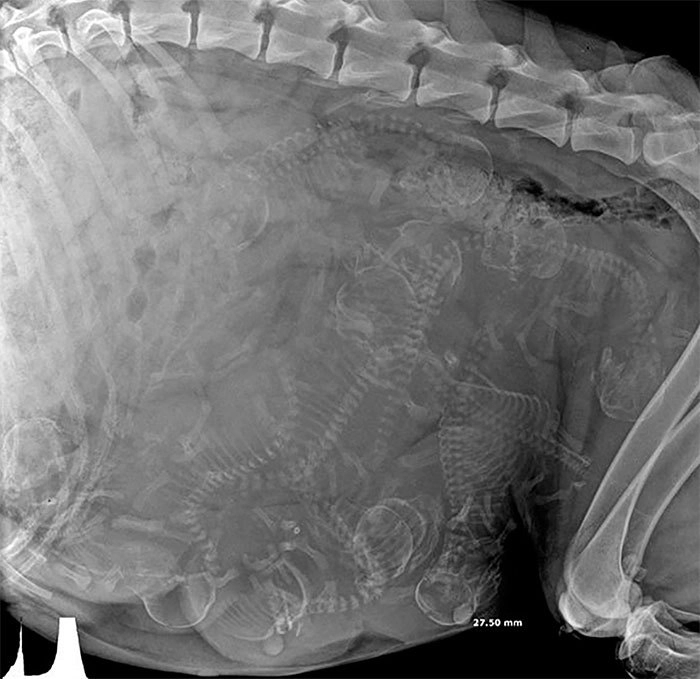

Рентген беременной собаки